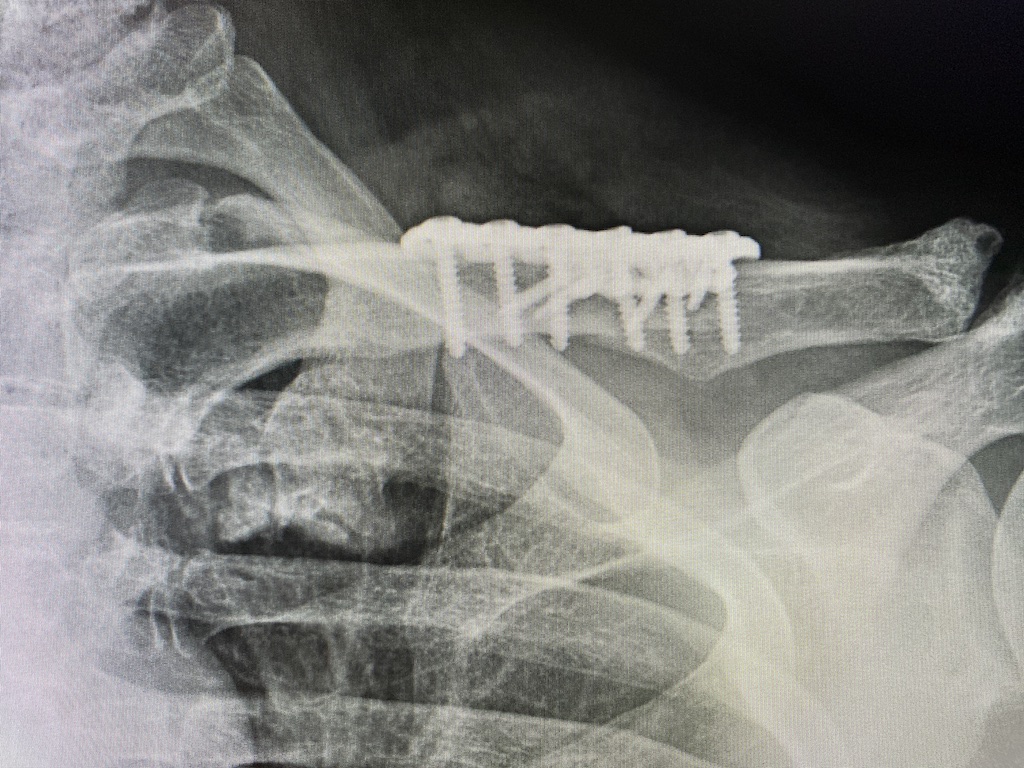

Clavicle Pin Fixation . Intramedullary devices, plates, and external. The purpose of this article is to demonstrate our technique of intramedullary (im) fixation of a midshaft clavicle fracture. An alternative to the current gold standard in operative treatment of displaced midshaft clavicle fractures (dmcf) using plate osteosynthesis, is internal fixation by means of intramedullary fixation devices. Operative fixation for acute displaced midshaft clavicle fractures provides improved functional outcomes and patient satisfaction over nonoperative treatment. Midshaft clavicle fractures are common traumatic injuries caused by a direct impact to the shoulder girdle and is most commonly seen in young, active adults.

Intramedullary devices, plates, and external. Midshaft clavicle fractures are common traumatic injuries caused by a direct impact to the shoulder girdle and is most commonly seen in young, active adults. An alternative to the current gold standard in operative treatment of displaced midshaft clavicle fractures (dmcf) using plate osteosynthesis, is internal fixation by means of intramedullary fixation devices. Operative fixation for acute displaced midshaft clavicle fractures provides improved functional outcomes and patient satisfaction over nonoperative treatment. The purpose of this article is to demonstrate our technique of intramedullary (im) fixation of a midshaft clavicle fracture.